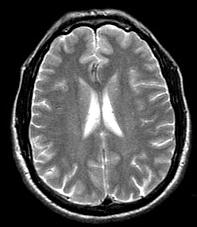

根据MRI表现,考虑为何种疾病 ( )A、脑型血吸虫病B、脑弓形体病C、脑囊虫病D、脑包虫病E、Lyme病

问题 根据MRI表现,考虑为何种疾病 ( )

选项 A、脑型血吸虫病 B、脑弓形体病 C、脑囊虫病 D、脑包虫病 E、Lyme病

答案 E